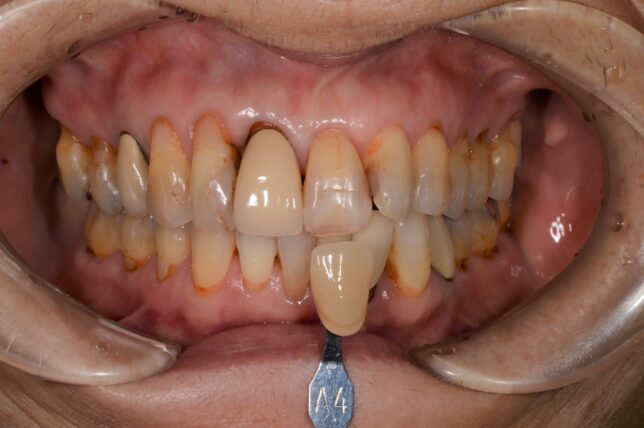

開始時

2週間後

ケース2は、ビフォーアフターの差があまり分からないかもしれませんね。

右上の前歯に合わせている色見本A4と比較すると2週間後の方が、色見本より白くなっているのが分かると思います。